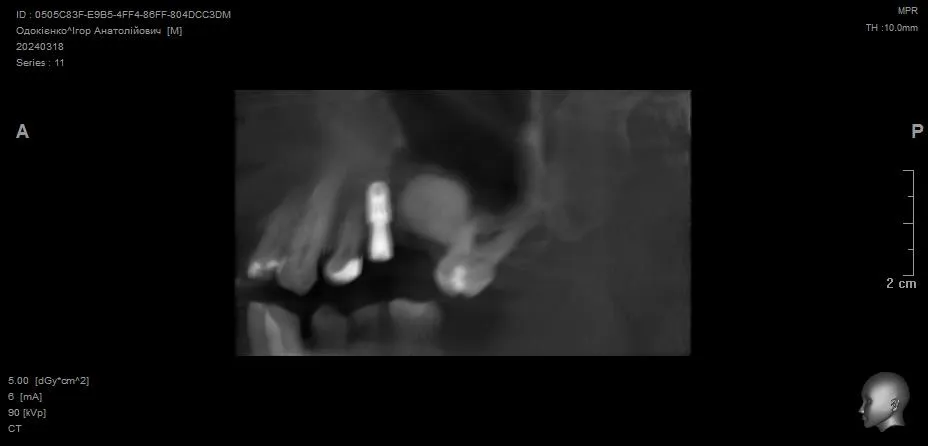

Видалення зуба 3.4 + Імплантація 3.4 3.5 3.7. Формувачі ясен. Система Neobiotech